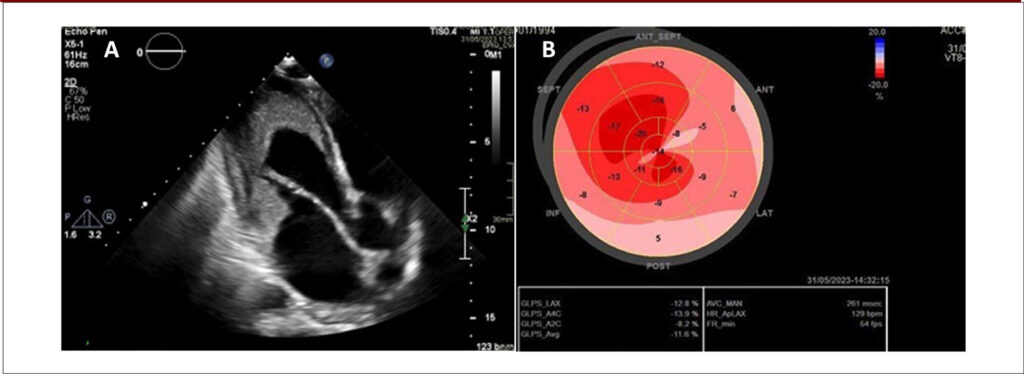

Insuficiência Mitral Importante e Disfunção Ventricular na Síndrome Hipereosinofílica: Relato de Caso

Este artigo descreve um caso de doença endomiocárdica eosinofílica, também conhecida como síndrome de Loeffler, uma manifestação da HES caracterizada pelo dano cardíaco mediado por eosinófilos. Apesar do tratamento adequado e controle da doença hematológica, o paciente evoluiu com disfunção sistólica biventricular e insuficiência mitral (IM) importante.